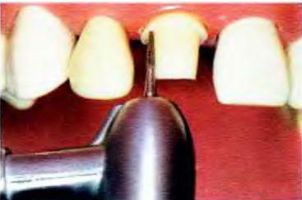

- Сошліфовиваніє твердих тканин зуба. Обсяг сошліфовиванія залежить від мінімальної товщини стінок коронки. Як правило, з усіх боків зуба сошліфовивать на 1,0-2,0 мм - знімається таку кількість твердих тканин зуба, яке може вмістити шар металу і кераміки.

- На рис. 3 ви можете побачити, як відбувається обточування зуба під коронку.

Мал. 3 Обточування зуба під коронку